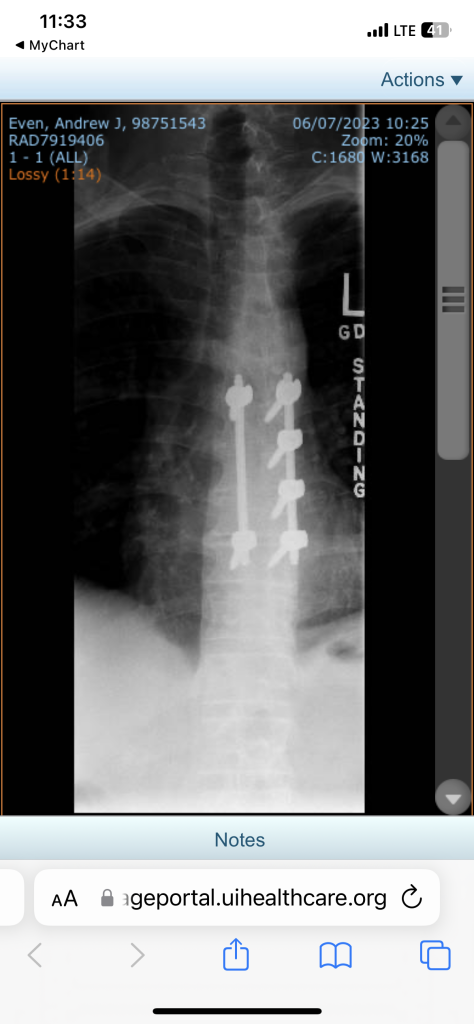

I got some hardware, yo!

Just reading this thread now. This happens to be kind of what I do professionally. It’s only a 4 level fusion and I don’t see any corpectomy cage. So probably just a decompression fusion. Hey maybe it was an intradural lesion (typically a schwanoma at thoracic level). That has excellent prognosis versus some spinal met (usually to vertebral body). The 8 hour duration you describe makes me think this was more likely an intradural lesion. Wish you the best in your recovery.

It was an intradural extramedullary lesion. Haven’t seen the final pathology report yet, but one of the neurosurgeons said they were leaning toward meningioma. They had to cut away parts of T8 and T9 to be able to get at the growth. Dr. Yamaguchi is a freaking rockstar! I admire what y’all do. I can’t even open a bag of M&M’s without spilling a third of the bag on the floor. :)

Meningioma and Schwanoma are basically the same thing. My original post said “meningioma” but I edited it lol. Central vs peripheral nervous system. They’re usually well circumscribed like a meatball and scoop out just as easily. Slow growing and typically no real recurrence. Cheers to the little things.

Although I have to admit, my first thought upon seeing that x-ray (standing??? uh, only if they hoisted me up!) was "Needs more cowbell."